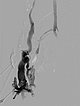

X-ray fluoroscopy after direct puncture of the venous malformation during sclerotherapy. As a result of closure of the communicating veins to the deep venous system, the VM is now isolated and can be sclerosed. After injection of contrast, no outflow of the contrast medium into the deep veins.